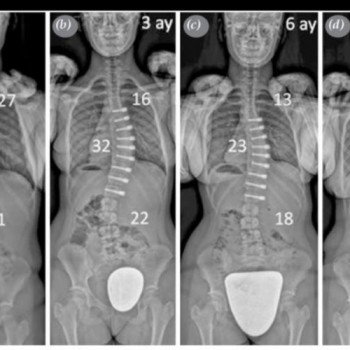

Multidisipliner Skolyoz Cerrahisinde VERTEBRAL Gövde Cerrahilerinin toraks bölümü Videotorakoskopik olarak tarafımca gerçekleştirilmektedir.